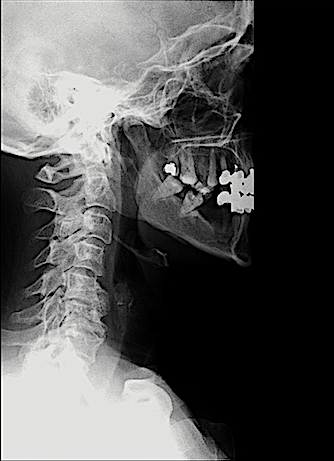

En mi opinión, las cajas intersomáticas atornilladas (CISA) son la mejor opción para corregir la cifosis cervical anterior, especialmente en patología multinivel. Además, a diferencia de «Cage Stand Alone» o caja cervical + placa; la lordosis conseguida se mantiene mejor en el tiempo.

En la técnica quirúrgica es clave asegurar una descompresión adecuada y respetar al máximo la anatomía de los platillos cervicales lo que, en algunos casos de espondilosis avanzada, es laborioso.

Aquí presento dos ejemplos.